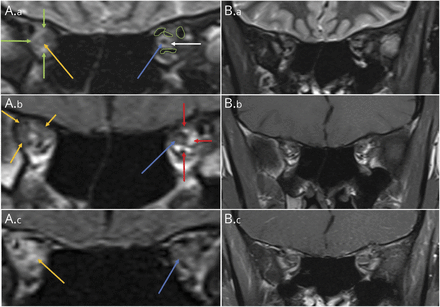

视神经炎的MRI发现有点令人费解,因为病人的陈述并不表明传入视觉障碍,而是一个传出。视神经疾病通常涉及视力丧失,颜色,视野赤字,经常一个美国(在单侧失明)。尽管可能出现视神经正常retro-orbital病态,损失是慢性萎缩应该注意一次。鉴于这种不一致的发现,neuro-ophthalmology咨询。检查发现传入视觉功能正常;然而,正如前面提到的,她并不是能够绑架或加合物的右眼。她传出的其余部分考试是毋庸置疑。因为她的神经检查没有透露一个视神经病变,仔细审查与放射学图像进行(图1中,A.a-A.c),揭示轨道顶端内弥漫性增强hyperintense信号损失的正常解剖细节,除了hyperintensity视神经内,确认一个轨道为她的病理过程可能的来源。

(一)冠状搅拌序列:正常离开轨道顶端显示正常相对hypointense信号左视神经(蓝色箭头),周围正常hyperintense CSF(白色箭头),进而是薄hypointense视神经鞘包围。小外围hypointense线性结构(绿色)中概述的轨道顶端的起源部分成像眼外肌肉。相比,异常对轨道顶端显示了一个漫射hyperintense搅拌信号(绿色箭头),损失的正常解剖细节。此外,对视神经的中部地区hyperintense搅拌信号(黄色箭头)。(A.b)冠状T1 precontrast形象:正常离开轨道顶端显示正常相对hypointense信号左视神经(蓝色箭头)和周围的CSF,进而被正常T1 hyperintense轨道顶端脂肪(红色箭头)。异常正确轨道顶端显示异常T1 hypointense信号(黄色箭头)的损失预计hyperintense T1信号轨道脂肪和损失的识别正确的视神经(因为类似的T1信号的视神经和周围的软组织异常在正确的轨道顶端)。(交流)冠状T1 postcontrast形象:左边(蓝色箭头)轨道顶端脂肪(以及正常的脂肪在所有其他解剖网站图片)失去了T1 hyperintense信号。正确的轨道顶端有明显异常增强的几乎整个顶点(黄色箭头)。(本科)冠状搅拌序列:解决异常正确轨道顶端和视神经hyperintense搅拌信号。现在轨道顶端对称和正常。 (B.b) Coronal T1 precontrast image: Sharp anatomic detail of the right orbital apex is restored. (B.c) Coronal T1 postcontrast with fat suppression image: There is complete resolution of abnormal enhancement of the right orbital apex and optic nerve. The orbital apices now are symmetric and normal.

病人经验开始连续3天,每天四甲基强的松龙100毫克口服强的松60毫克每日紧随其后。她看到neuro-ophthalmology诊所10天后,她在报道她复视有显著提高,只有2-diopter esophoria右边的目光。测试显示正常免疫球蛋白子类IgG1、2和3;然而,IgG-4 97.1(正常4 - 86 mg / dL),和总免疫球蛋白是1914(正常700 - 1600 mg / dL)。她在强的松60毫克每日维护,一个月后,她报告完整的决议复视。在4个月的时间间隔重复轨道成像显示分辨率的异常增强轨道顶端(图1中,B.a-B.c)。